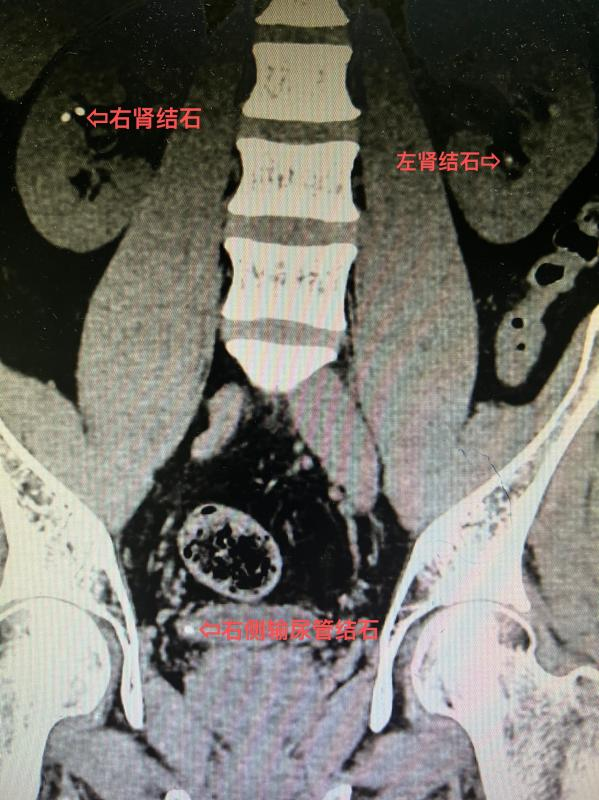

10 年前患者检查发现双肾结石,近年来反复出现腰部疼痛,在外院多次行体外冲击波碎石,未见结石排出,症状也没有改善,严重影响了工作和生活。后到 市中医医院 泌尿外科就诊,泌尿外科拓鹏飞副主任医师接诊后行 CT 显示:双肾多发结石、右侧输尿管结石。